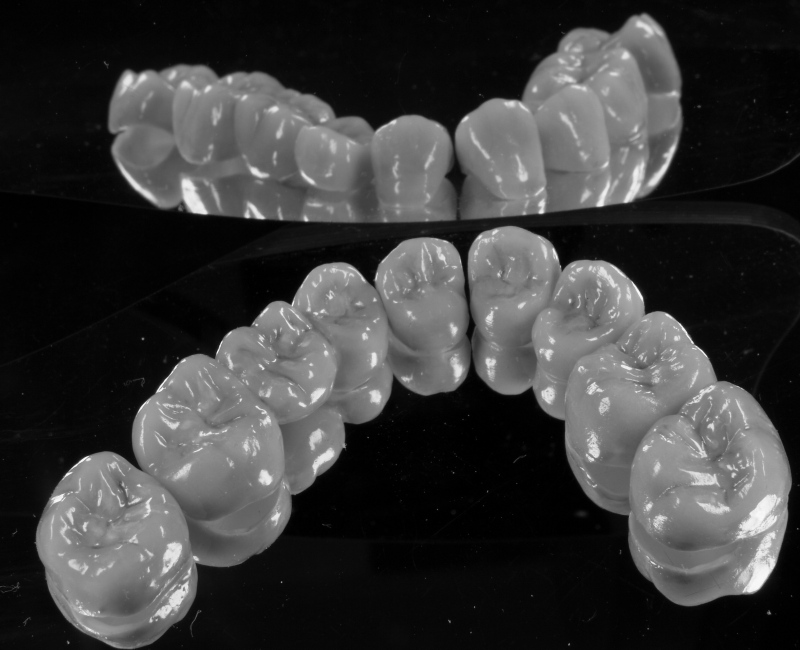

Keine Metalle im Mund

Keramikstufen

Meisterarbeit von Peter Dengel